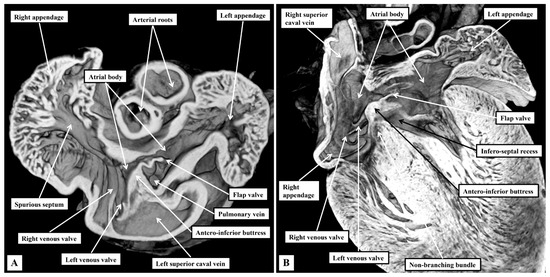

Background: Since the study of Lev and Thaemert in 1973, little has been published concerning the overall arrangement of the murine conduction tissues, in particular with relation to gross anatomical landmarks. We recently emphasised the potential va...